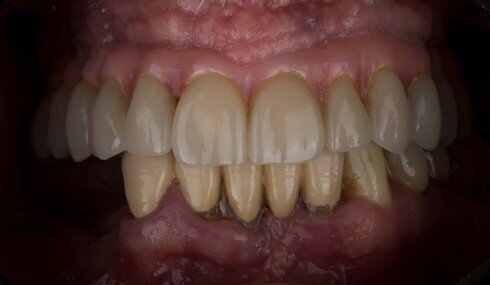

Nino - detail finálního úsměvu

Nino po třech letech kouření - detail